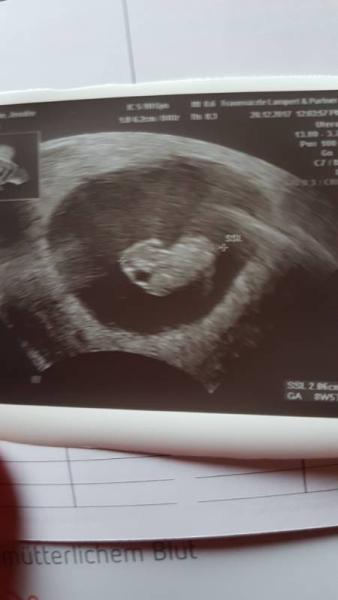

Ich hatte heute auch endlich meinen ersten Termin beim Frauenarzt und es ist alles gut. Auch wenn es die dritte Schwangerschaft ist, habe ich trotzdem fast geweint als ich das Herzchen hab schlagen sehen. Das ist so ein schöner Moment. Ich bin so glücklich und kann mich jetzt richtig freuen da es für mich jetzt real ist.

Wie schön, ich freue mich für dich und ein sehr Süßes Bild